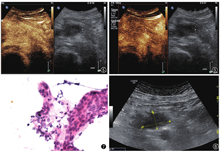

正电子发射型计算机断层显像(positron emission computed tomography,PET/CT):胰头区软组织肿块,代谢异常增高,胰头周围代谢增高淋巴结,双肺上叶及右肺下叶背段斑片样代谢增高,建议首先除外IgG4相关疾病;胰腺体尾部代谢增高灶,考虑炎性改变可能性大。完善患者血清IgG亚类测定(4项):IgG3:18.4 mg/dl,IgG4 188 mg/dl(正常值8~140 mg/dl)。血清IgG4偏高,但低于正常值两倍,临床意义有限,因约5%的正常对照和10%的胰腺癌患者血清IgG4水平也升高,故仍不能明确诊断自身免疫性胰腺炎(autoimmune pancreatitis,AIP)[1]。且CT复查提示该占位病变体积较前增大,因而又先后两次行超声引导下经皮胰头占位病变细胞学穿刺,病理诊断均未见瘤细胞(图7)。

鉴于胰头肿物3次穿刺病理均未见瘤细胞,且复查CA19-9(-),IgG4升高至287.9 mg/dl,随着病情进展,患者出现门静脉血栓伴门脉主干旁海绵样变性、侧支循环形成,临床诊断为肿块型自身免疫性胰腺炎可能性大,但恶性占位病变待除外,故给予激素实验性治疗后患者ESR、hsCRP下降,疼痛症状明显改善。3个月后超声复诊,肿块体积较前明显减小(图8),IgG4 63.9 mg/dl。目前随诊3年,患者一般情况较好,病灶较前明显减小。